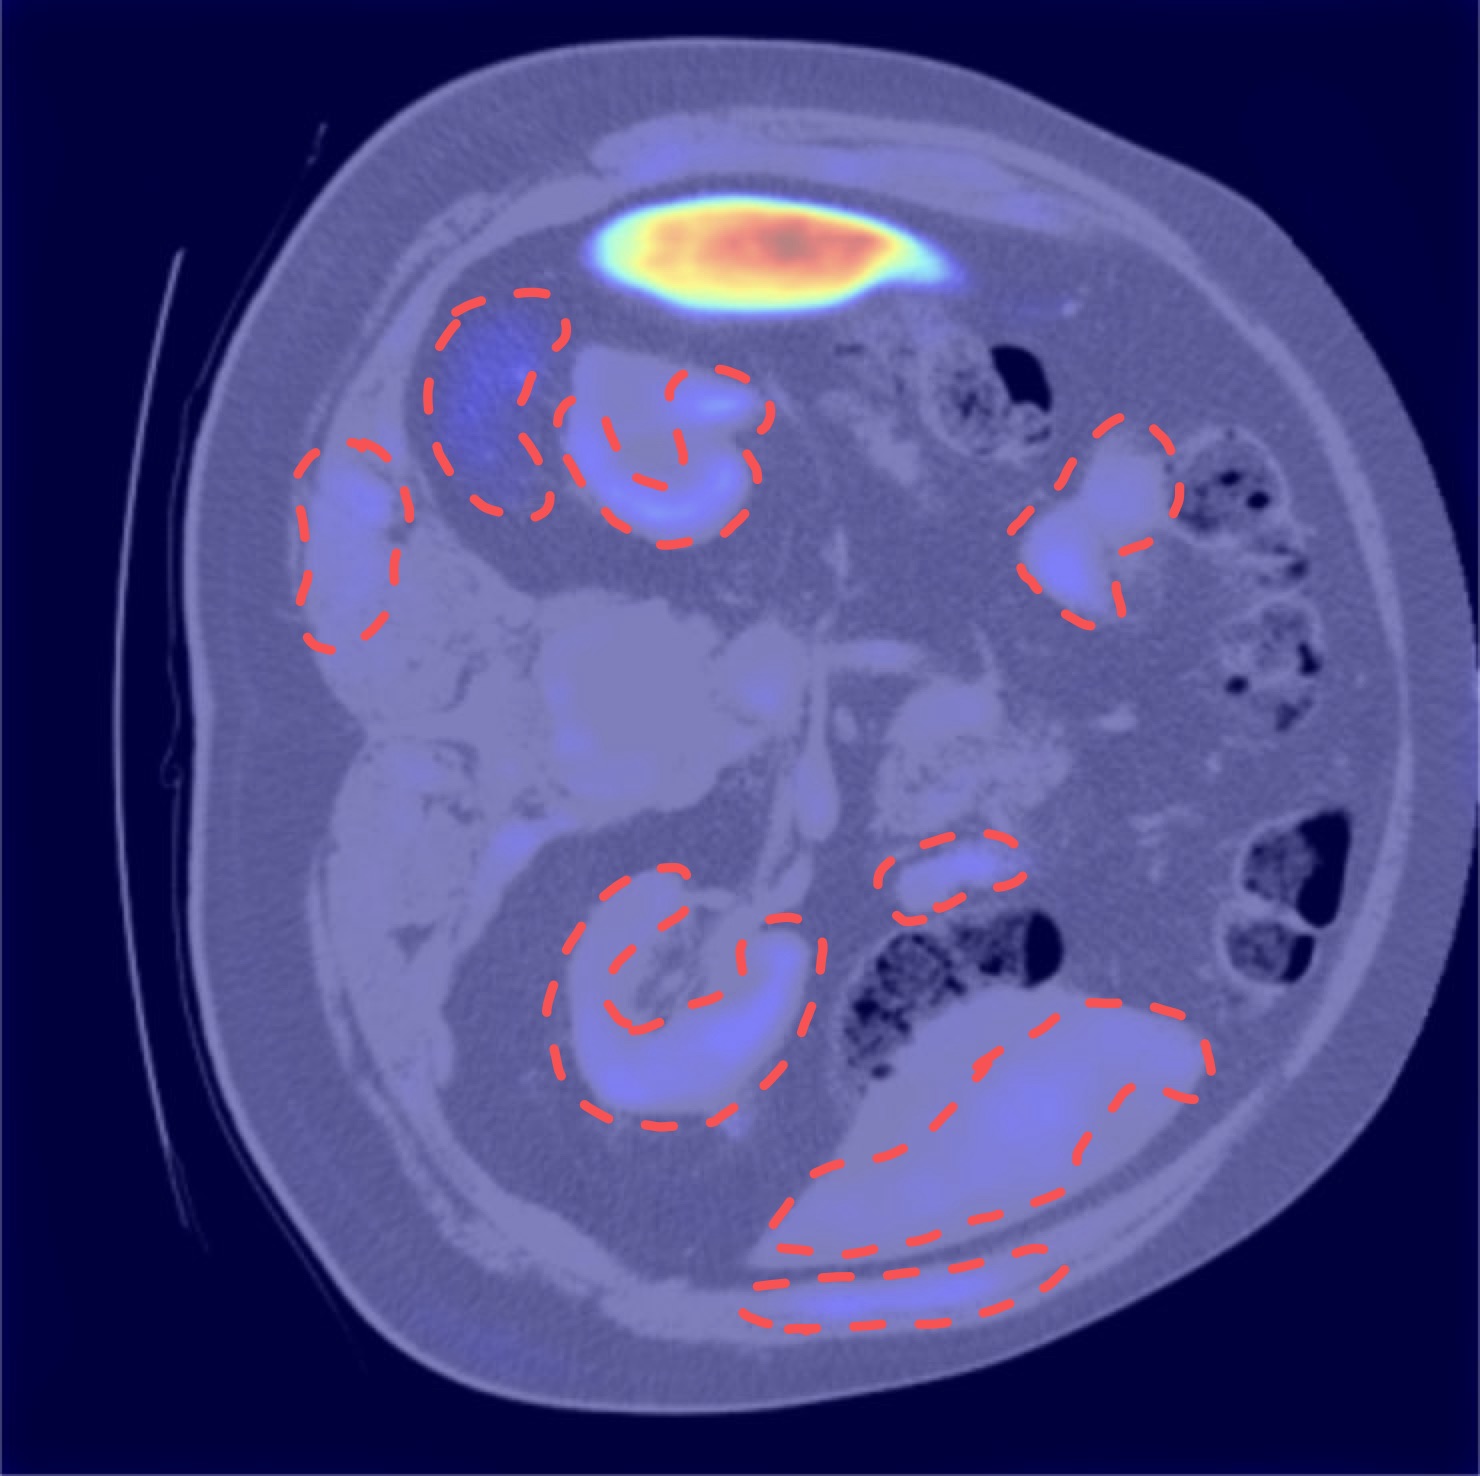

EU-Nets consistently outperform their baseline counterparts, particularly in terms of stability, demonstrating robustness across different cross-validation folds and diverse data distributions. Moreover, integrating MHEX+ introduces only a minimal increase in model parameters (<0.1M). For overall performance comparison, see Table 4, and for individual sample results, refer to the Pred row in Figure 4.

Although both MHEX+ and Grad-CAM highlight important regions, they rely on fundamentally different mechanisms. Grad-CAM computes pixel-wise gradients, reproducing the segmentation output rather than providing deeper insights.

In contrast, MHEX+ leverages class-level equivalent convolution kernels to analyze how the network attends to each class. By aggregating learned weights instead of focusing solely on pixel-level gradients, MHEX+ captures multi-scale feature responses across decoder stages, highlighting relevant regions beyond the segmented target, such as liver and kidney areas. For comparison, see Figure 5.

To evaluate the validity of our MHEX+ based uncertainty estimation (MU), we compare MU maps with Deep Ensemble uncertainty (DEU) maps (Section 3.5).

We conducted experiments on the MSD-Heart dataset using 50 randomly selected samples and tested four proposed EU-Nets. Each model’s uncertainty was computed via the MU approach, and the resulting maps were aggregated into a single composite visualization (Fig. 6, last column). For single uncertainty samples, see Figure 4, last row. DEU maps (Fig. 6) were obtained using entropy- and variance-based uncertainty estimation (Section 3.5).